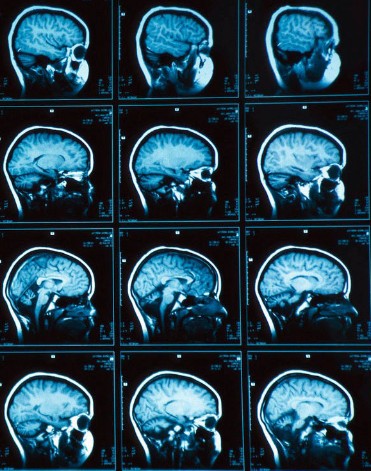

Те, кто не сталкивался с этой методикой, не знают, как выглядит снимок МРТ, фото его можно найти в свободном доступе в интернете. Обычно это огромный лист, похожий на результат рентгена, на котором представлены данные послойного сканирования исследуемой области.

Отметим, что результаты МРТ на фото пациент или люди без специального медицинского образования не смогут корректно интерпретировать - расшифровывать и описывать их должны только специалисты.